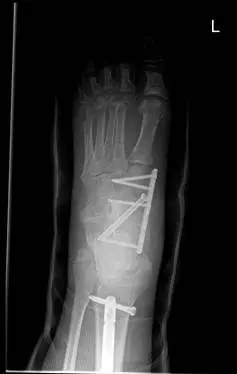

These are pics of an open midfoot fracture and dislocation after a motor vehicle accident.

These are pics of the external fixator on to hold temporary reduction prior to internal fixation